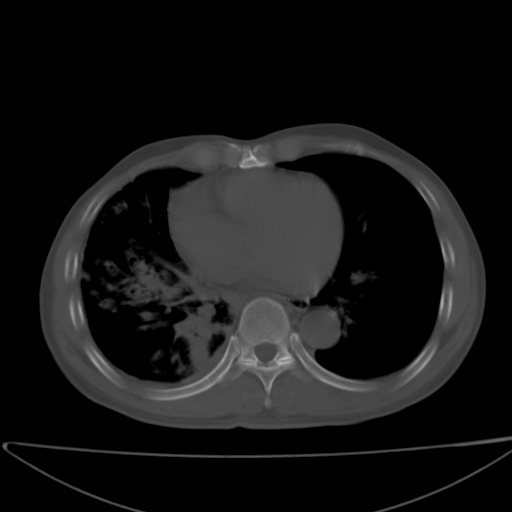

以下是引用jsgdoctor在2008-11-6 22:12:00的发言:[br]右主支气管壁明显增厚,管腔狭窄.考虑为右侧中央型肺癌伴阻塞性炎症\\肺脓肿.

以下是引用zjzjr在2008-11-6 20:25:00的发言:[br]中心型肺ca,合并阻塞性肺炎

以下是引用zsl6918在2008-11-6 19:43:00的发言:[br]右侧中心性肺癌(鳞癌)